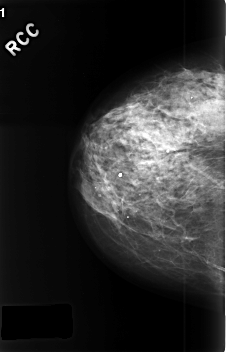

ics_version 1.0 filename C-0379-1 DATE_OF_STUDY 23 4 1996 PATIENT_AGE 67 FILM FILM_TYPE REGULAR DENSITY 3 DATE_DIGITIZED 3 11 1998 DIGITIZER LUMISYS LASER SEQUENCE LEFT_CC LINES 4520 PIXELS_PER_LINE 3008 BITS_PER_PIXEL 12 RESOLUTION 50 OVERLAY LEFT_MLO LINES 4504 PIXELS_PER_LINE 3016 BITS_PER_PIXEL 12 RESOLUTION 50 OVERLAY RIGHT_CC LINES 4568 PIXELS_PER_LINE 2936 BITS_PER_PIXEL 12 RESOLUTION 50 NON_OVERLAY RIGHT_MLO LINES 4568 PIXELS_PER_LINE 2968 BITS_PER_PIXEL 12 RESOLUTION 50 NON_OVERLAY |